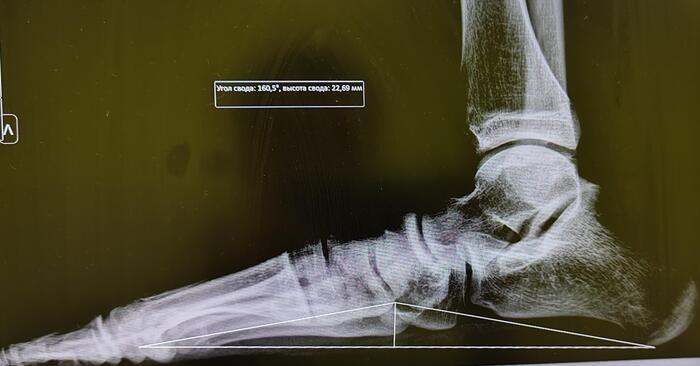

Продольное плоскостопие 3 ст

Описание снимков: на Р-граммах стоп с нагрузкой по Богданову: Высота свода левой стопы 22мм,угол продольного свода-160 град. Высота свода правой стопы 30 мм, угол продольного свода-153 град. Заключение: Двустороннее продольное плоскостопие 2(второй) ст. справа,3(третьей) ст. слева.

Верхняя точка треугольника на правой стопе, незначительно смещена проксимально, на итоговое заключение не влияет.

На основании 565 постановления, статьи 68(Плоскостопие и другие деформации стопы),диагноз продольное плоскостопие 3 ст. соответствует пункту в-В(ограниченно годен к военной службе).